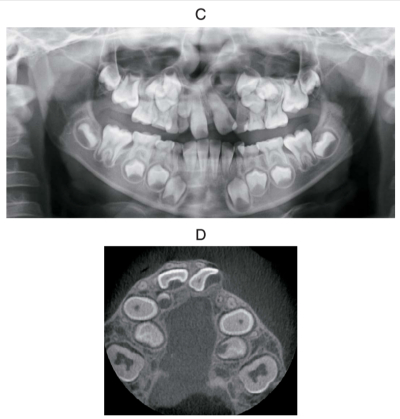

7歳の男児。前歯の歯並びが悪いことを主訴として来院した。口唇裂と口蓋裂に対する手術の既往がある。初診時の顔面写真、口腔内写真、エックス線画像及び歯科用コーンビーム CTを別に示す。セファロ分析の結果を図に示す。まず行うのはどれか。2つ選べ。